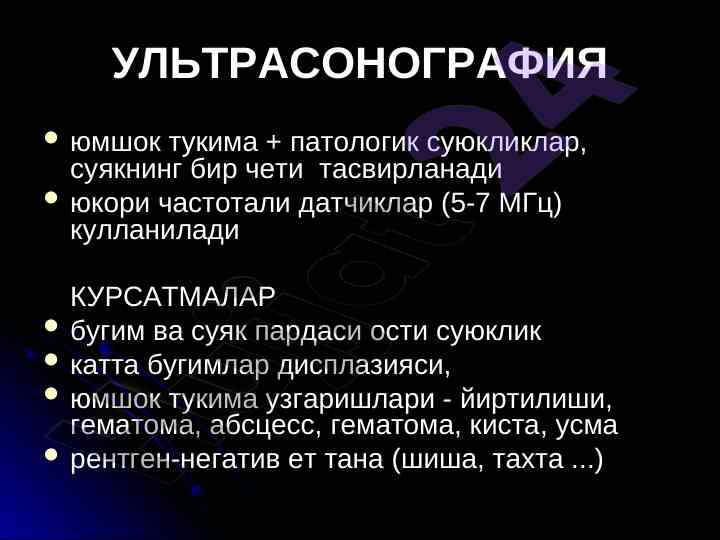

Рентгенография, ультрасонография ва сцинтиграфия усуллари тянч-харакат тизими касалликлари диагностикасида муhim аҳамиятга эга. Инсон организмининг юз бериши мумкин бўлган ўзгаришларни аниқлашда муҳим рол ўйнайди.